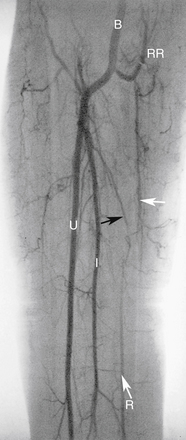

РИСУНОК 13-6 Высокое начало лучевой артерии. Артериограммы руки (А) и предплечья (Б) демонстрируют высокое отхождение лучевой артерии (R; стрелки ) на уровне средней плечевой кости. Б — плечевая артерия; I, межкостная артерия; U, локтевая артерия.

РИСУНОК 13-7. Коллатеральное кровообращение при окклюзии лучевой артерии. Дистальная часть лучевой артерии (R; большая стрелка ) заполняется в основном ретроградно из поверхностной и глубокой ладонных дуг (не показано). Антеградное коллатеральное кровоснабжение также обеспечивается возвратной лучевой артерией (RR; белые стрелки ) и межкостной артерией (I; черная стрелка ). Б — плечевая артерия; U, локтевая артерия.